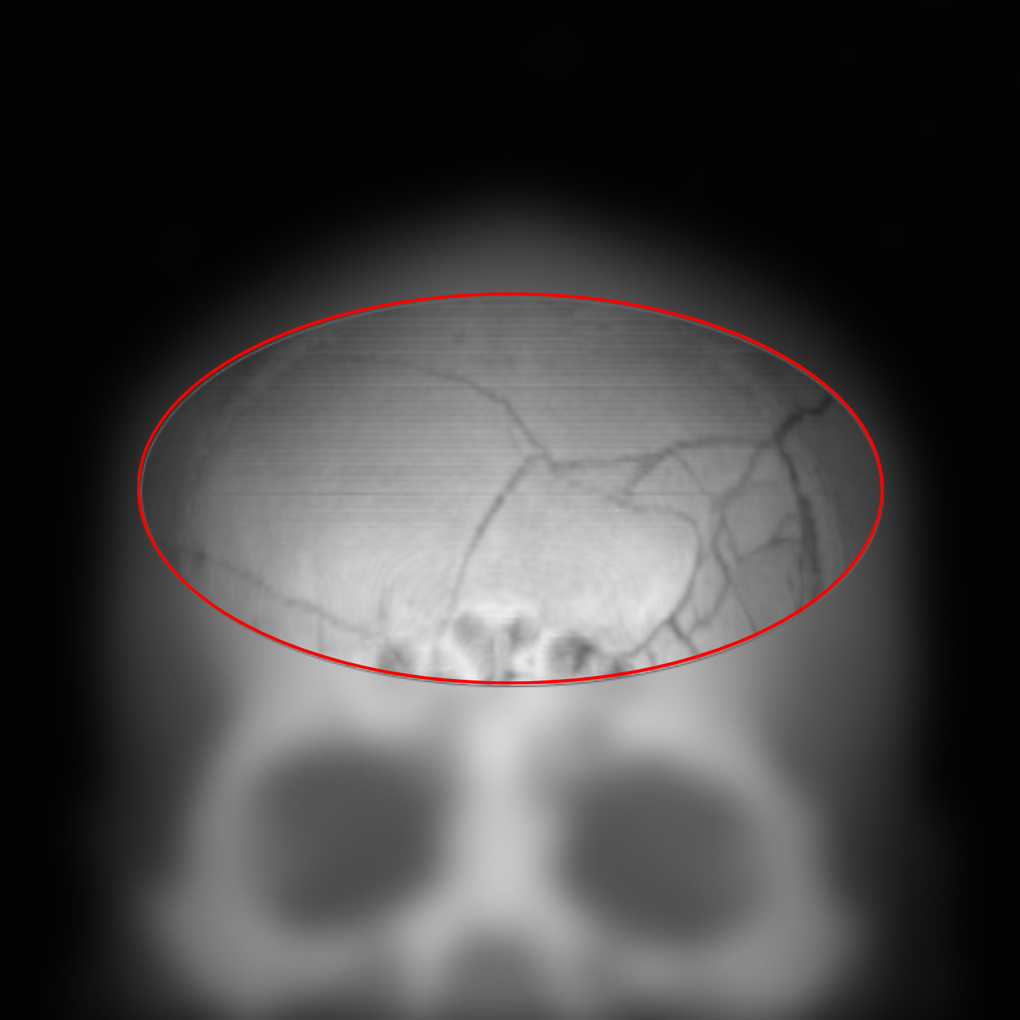

Khoảng 3 tháng trước, bệnh nhân C.V.N (27 tuổi) bị tai nạn giao thông, đến BVĐK Hồng Ngọc - Phúc Trường Minh cấp cứu trong tình trạng choáng váng, sưng nề vùng đầu. Kết quả chụp CT sọ não cho thấy có chấn thương sọ não kèm vỡ xương trán phức tạp nhưng không phát hiện tụ máu, xuất huyết hay rò rỉ dịch trong màng não nên chưa cần can thiệp phẫu thuật. Sau 10 ngày theo dõi, điều trị bảo tồn, bệnh nhân ổn định sức khỏe và được xuất viện, tiếp tục theo dõi chấn thương tại nhà trong 3-6 tháng, hạn chế vận động mạnh.

Phim chụp vùng xương trán bệnh nhân N bị vỡ phức tạp không gây xuất huyết, tụ máu não (Ảnh: BVCC).